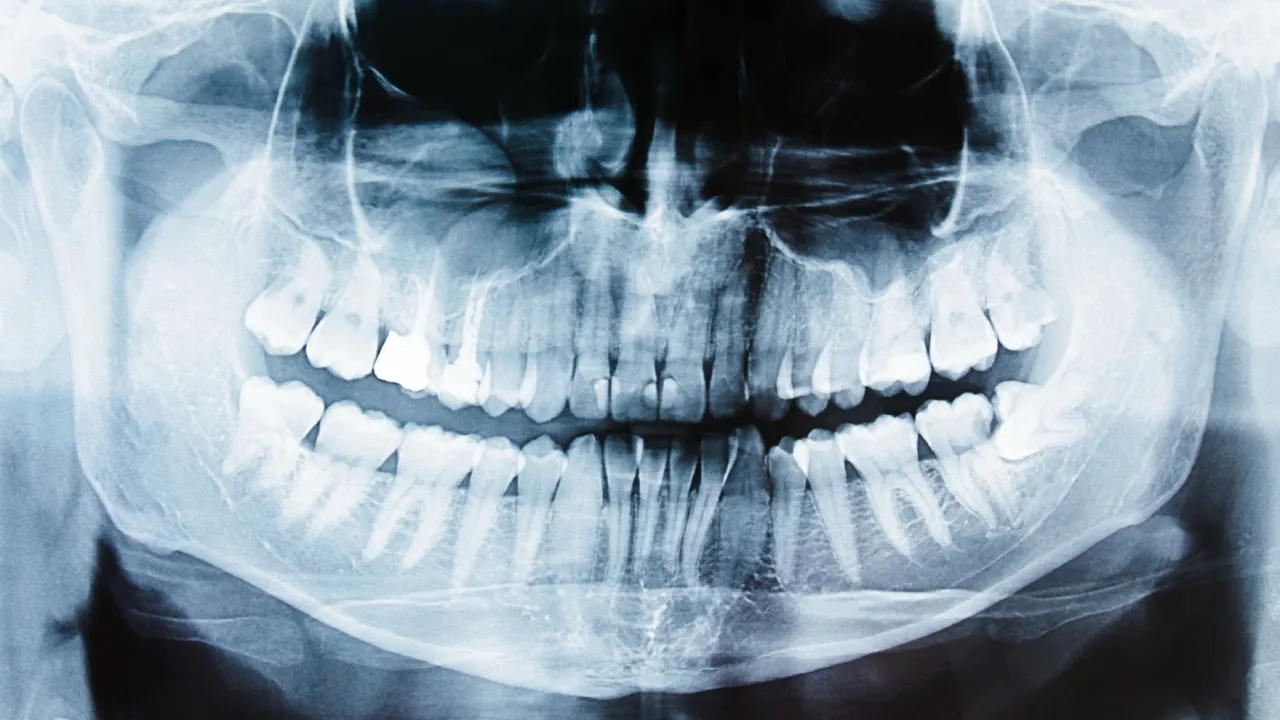

Kluczowym elementem diagnostyki w przypadku ropy w dziąśle jest wykonanie zdjęcia rentgenowskiego. Najczęściej jest to zdjęcie punktowe, które pozwala mi precyzyjnie zlokalizować źródło problemu. Na zdjęciu RTG mogę zobaczyć zmiany w kości wokół wierzchołka korzenia zęba (tzw. przejaśnienie), które świadczą o ropniu okołowierzchołkowym, ocenić stan kości w przypadku paradontozy, a także wykryć pęknięcia korzenia czy zatrzymane zęby. Bez RTG postawienie trafnej diagnozy jest często niemożliwe.